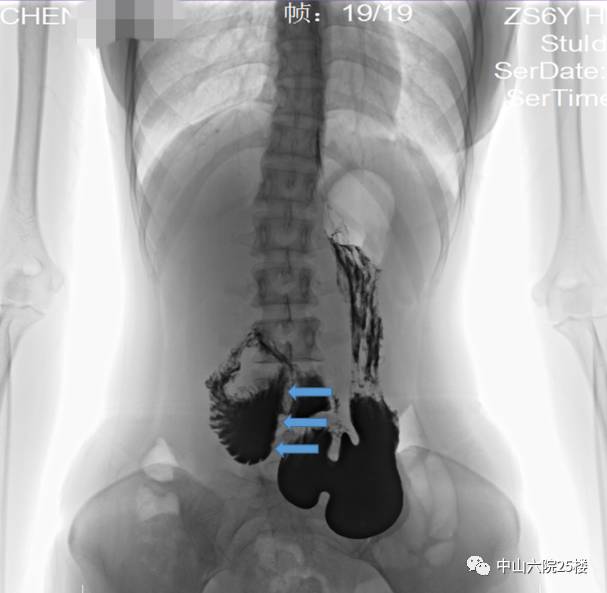

小青几经辗转,找到了陈双教授。我们先给她做了个食道吞钡上消化道造影,果然不出我们所料,就是这个病!

(箭头所指为十二指肠受压迫的地方,笔直笔直的,又称“笔杆症”。十二指肠近端扩张)